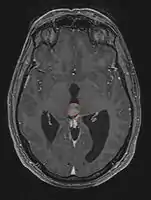

Pineal Gland Tumors

Clinical Presentation

- Determined by the spatial anatomy and direction of growth

- Obstruction of aquaduct: hydrocephalus presenting as headaches, nausea, vomiting

- Compromise of superior colliculus: vertical gaze palsy, pupillary and oculomotor nerve paresis (Parinaud syndrome)

- Progressive growth: cranial nerve neuropathies, hypothalamic dysfunction

- Work-up includes MRI, CSF, serum markers for bHCG and AFP